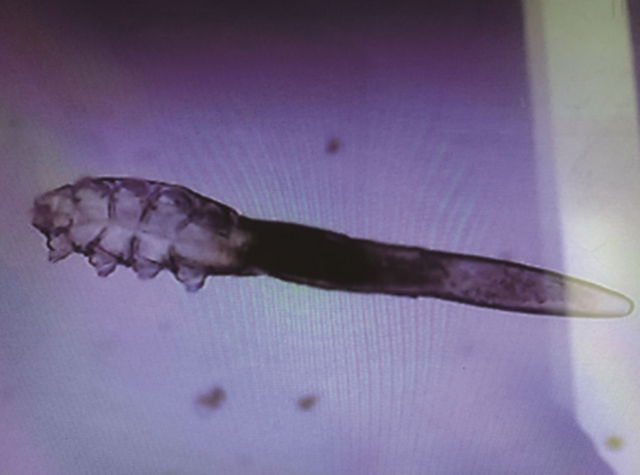

(醫生檢查發現陳小姐的睫毛根部長滿蠕形蟎蟲,翻攝自中媒)

綜合中媒報導,陳小姐因為天生睫毛較短,因此養成了定期去種睫毛的習慣。但最近一次卻發現,自己眼皮經常劇烈發癢,還有乾眼症的狀況。最嚇人的是,睫毛明顯稀疏,不只假睫毛,連真睫毛也快掉光了。 陳小姐驚覺事態嚴重,前往溫州市中西醫結合醫院眼科看診,經醫生檢查後,發現陳小姐的睫毛根部長滿了蠕形蟎蟲,確診為蠕形蟎感染引起的眼瞼炎。